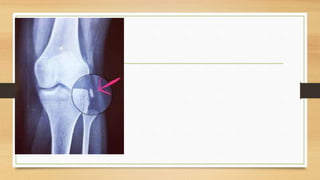

EXAMENES AUXILIARES

Linea de Blumenssat,

cicatriz del cartílago

hialino

EXAMENES AUXILIARES Linea deBlumenssat, cicatriz del cartílago hialino